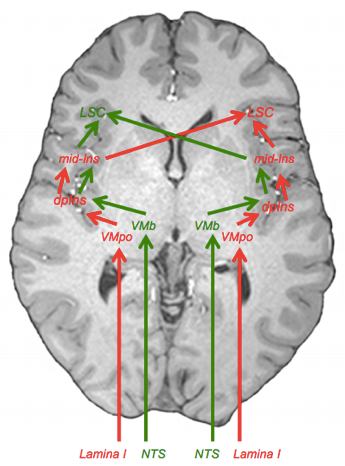

vad händer när vi går ifrån VMpo tll insula kopplat till interoception?

Ifrån VMpo går singaler till dorsla posterioa insula (även känd som Interoceptiva kortex).

- Vekar likt S1 och gör så vi kan känna av var ifrån smärtan kommer ifrån

- Obs kom ihåg att de tidigare överköras! Alltså så kommer smärta i höger hand gå till vänster hjärnhalva.

- Kommer först till dorsala insula där filtrering sker men igen tolkning

- Sedan till mid-insula

- Där tolkning av smärta sker

- Sedan går det till Limbiska sensoriska cortex

- Där koppling ifrån flera saker sker, så som Vicerala, amygdala och hypotalmus

varförklara bilden?

- Lamina 1 singalerna kommer då gå den Röda vägen i bilden sedan

- Beskrivs som ovan som:

- Kommer först till dorsala insula där filtrering sker men igen tolkning

- Sedan till mid-insula

- Där tolkning av smärta sker

- Sedan går det till Limbiska sensoriska cortex

- Där koppling ifrån flera saker sker, så som Vicerala, amygdala och hypotalmus

- Beskrivs som ovan som:

- Dessa är mer sympatiska och ”starkare” signaler som ger negativa känslor och energiförbrukning

- Kommer gå till högra hjärnhalvans Limbiska senoriska krotex

- Alltså så kommer de ifrån höger gå rakt hit, och de ifrån vänster kommer överkorsa hit

- Medan vicerala parasymatiska signaler går den gröna vägen

- De är snällare signaler som ger oss energiuppladdning och positiva känslor

- Går till vänstra limbiska cortex (hälften överkorsar hit och hälften går redan hit)